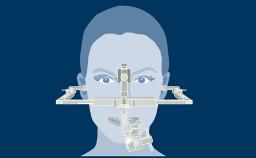

A systematic approach to receive the necessary preoperative information increases the likelihood that all relevant facets are elucidated.

In addition, it will assist the clinician in identifying potential risk factors for the planned treatment and in revealing relative and absolute contraindications.